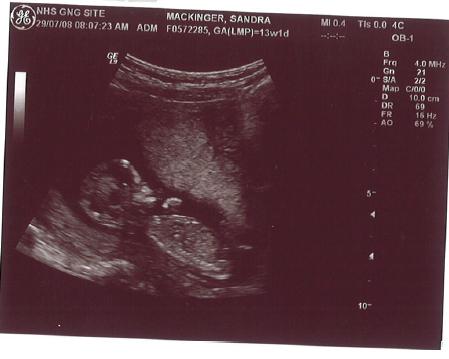

12. Schwangerschaftswoche:

Breakdance in Mama´s Bauch.